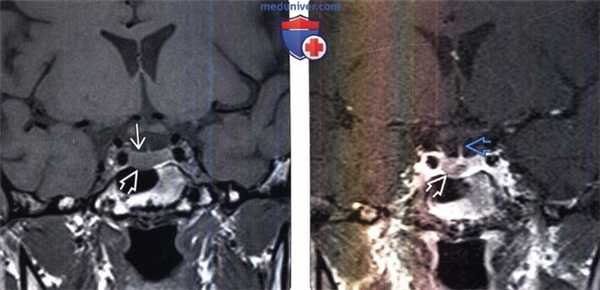

(Слева) МРТ, Т1 -ВИ, корональный срез: у женщины 32 лет с повышенным уровнем пролактина и галактореей визуализируется минимальное увеличение правых отделов гипофиза с легким истончением дна турецкого седла.

(Справа) МРТ, постконтрастное Т1-ВИ: у этой же пациентки в правых передних отделах гипофиза определяется объемное образование, которое накапливает контраст в меньшей степени, чем нормальная ткань гипофиза слева. Воронка имеет нормальное срединное расположение. Было проведено транссфеноидальное хирургическое удаление опухоли после выявления ее роста на фоне медикаментозной терапии. При резекции была выявлена пролактинома.

(Слева) МРТ, постконтрастное Т1 -ВИ, корональный срез: в структуре слегка увеличенного гипофиза визуализируется очаг, менее интенсивно накапливающий контраст. У этого паци ента отсутствовала симптоматика, и образование было выявлено случайно. «Инсиденталомы» гипофиза встречаются часто и могут быть нефункционирующими аденомами или неопухолевыми кистами.

(Справа) МРТ, постконтрастное Т1-ВИ, корональный срез: у пациента 36 лет с синдромом Кушинга в правых отделах железы визуализируется объемное образование, представляющее собой АКТГ -секрети-рующую аденому гипофиза. АКТГ-секретирующие опухоли часто локализуются в центральных отделах железы.